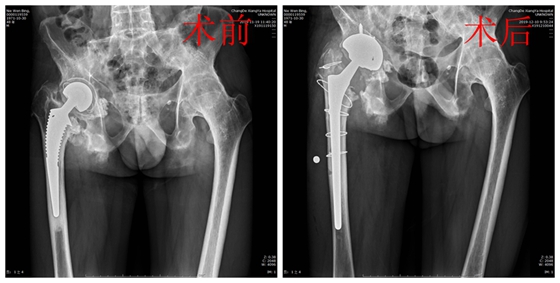

骨科主任张朝跃教授就聂先生的病情组织全科进行病例讨论。患者为强直性脊柱炎导致的左髋关节融合及右髋关节置换术后假体松动,两侧髋部均有手术指征。但考虑到其体质较差,手术时间长,出血较多,患者无法耐受,所以暂且行右髋关节翻修术。经过充分论证后,制定了周密的术前准备、手术方案以及应急预案。手术采用后外侧入路对周围组织分离保护,切开瘢痕化的关节囊,将关节脱位,行ETO截骨去除股骨假体后,装入生物型髋关节假体,C型臂透视下满意,假体固定可靠。经过3小时手术,成功为患者实施髋关节翻修手术。术后患者生命体征正常,髋部疼痛症状明显减轻,顺利出院。

术前、术后骨盆正位X线片